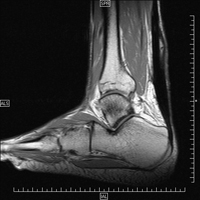

Es el tendón más grueso del cuerpo humano y se localiza en la parte posterior del tobillo. Recibe su nombre de Aquiles, héroe de la guerra de Troya inmortalizado por Homero en la Ilíada. La debilidad de Aquiles estaba en su talón.

Las sobrecargas del tendón de Aquiles provocan pequeñas lesiones que con el tiempo generan graves problemas. Los tipos de lesiones más frecuentes son: tendinitis, tendinosis y roturas. Las tendinitis y tendinosis precisan reposo, talonera de descarga, AINE y fisioterapia. La inyección de factores de crecimiento puede ser efectiva en el tratamiento de estas lesiones. Las roturas de Aquiles (tanto agudas como crónicas) necesitan cirugía para recuperar la fuerza que tenía el paciente antes de la cirugía.